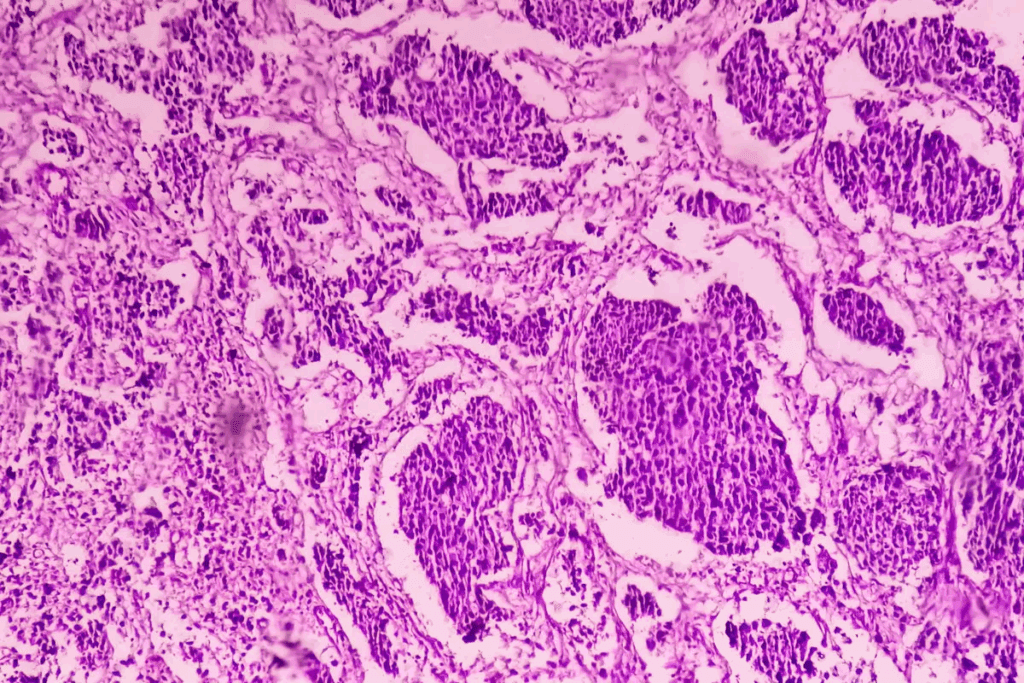

Understanding Bladder Cancer Basics

Bladder cancer starts when bladder cells grow out of control. The most common type is urothelial carcinoma. Smoking, age, and chemical exposure are risk factors. Knowing this helps us see how smoking leads to bladder cancer.